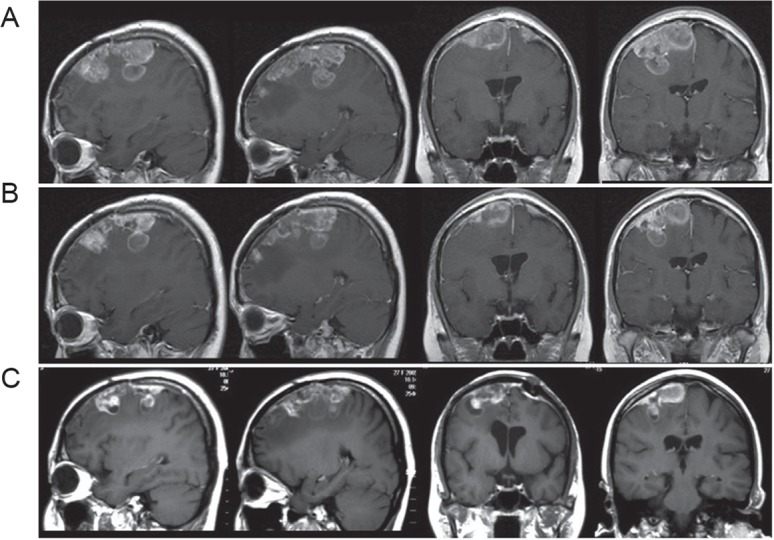

自2005年以来,我们应用BNCT来治疗强化治疗后复发或难治性高级别脑膜瘤。到目前为止,我们已经用BNCT治疗了32例高级别脑膜瘤。20例随访4年以上,经BNCT诊断后MSTs分别为14.1个月(95%CI:8.6-40.4)和45.7个月(95%CI:32.4-70.7)。与图3中所示的病例一样,所有病例对BNCT反应良好,且在BNCT后肿物收缩良好。

图3:BNCT对高级别脑膜瘤的代表性治疗效果。25岁女性,有横纹肌样脑膜瘤(who三级)重复复发史,即使经过多次手术和SRSs。轴位、冠状面及矢状位的连续增强磁共振影像显示,右额叶肿瘤在最后一次GKS后迅速生长,在BNCT后4个月内逐渐减少。在BNCT前,她表现为左偏瘫,只能靠轮椅才能行动,而BNCT后一周内她就开始走路了。A:BNCT前一周;B:BNCT后两周;C:BNCT后4个月。BNCT:硼中子俘获治疗,GKS:伽玛刀手术,SRS:立体定向放射外科。